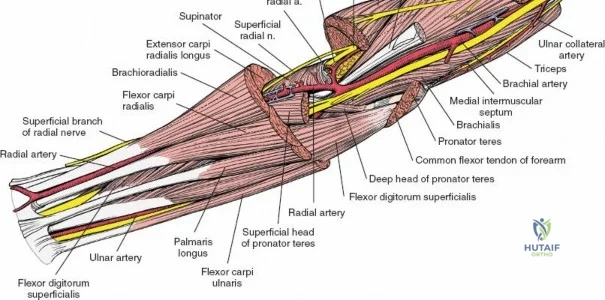

The anterior approach to the radius is an elegant example of utilizing true internervous planes to achieve deep exposure without denervating musculature. Distally, the internervous plane lies between the brachioradialis muscle (innervated by the radial nerve) and the flexor carpi radialis muscle (innervated by the median nerve). Proximally, the plane transitions to lie between the brachioradialis (radial nerve) and the pronator teres muscle (median nerve). Exploiting this plane allows the surgeon to mobilize the entire lateral muscular compartment (the "mobile wad" comprising the brachioradialis, extensor carpi radialis longus, and extensor carpi radialis brevis) away from the anterior flexor compartment.

Vascular Anatomy and the Recurrent Radial Leash

The radial artery runs distally through the forearm, initially lying deep to the brachioradialis muscle before becoming more superficial in the distal third. Just distal to the elbow joint, the radial artery gives off a complex network of vessels known as the recurrent radial artery leash (the "leash of Henry"). These vessels branch laterally to supply the brachioradialis and the mobile wad. To successfully mobilize the brachioradialis laterally and access the proximal radius, this entire leash of vessels must be meticulously isolated, ligated, and divided. Failure to do so will tether the brachioradialis, prevent adequate exposure, and risk severe postoperative hematoma from avulsed vessels.

Incise the deep fascia of the forearm in line with the skin incision. The initial goal is to identify the medial border of the brachioradialis as it courses down the forearm. It is a common pitfall to search for this border too far laterally. At the level of the elbow, the brachioradialis is expansive and extends almost halfway across the anterior forearm. It is surprisingly easy to mistake the plane between the brachioradialis and the extensor carpi radialis longus for the correct intermuscular plane.

To confirm the correct plane, look for the superficial branch of the radial nerve. This sensory nerve runs on the undersurface of the brachioradialis muscle. Once the true medial edge of the brachioradialis is found, develop the plane between it and the pronator teres (proximally) or the flexor carpi radialis (distally). Retract the brachioradialis laterally, taking care to keep the superficial radial nerve attached to its undersurface to protect it from traction injury.

Managing the Radial Artery and Recurrent Leash

As the brachioradialis is retracted laterally, the radial artery and its venae comitantes are exposed lying deep in the middle part of the forearm, closely related to the medial edge of the wound. Begin dissection distally and work proximally. Just below the elbow joint, the radial artery gives off the recurrent radial artery and a leash of muscular branches that dive laterally into the brachioradialis.

This leash must be meticulously managed. Take time to isolate, ligate, and divide these vessels. Do not attempt to use electrocautery alone on the larger branches, and absolutely avoid blunt avulsion. Avulsion of these vessels from the main radial artery is a potent cause of difficult-to-control intraoperative bleeding and severe postoperative hematoma. Once the leash is divided, the brachioradialis can be fully mobilized laterally, exposing the deep muscular layer.

Exposing the proximal third of the radius requires extreme vigilance due to the proximity of the posterior interosseous nerve. The key anatomical landmark here is the insertion of the biceps tendon. Follow the biceps tendon distally to its insertion on the bicipital tuberosity of the radius. A small bursa lies just lateral to the tendon; incise this bursa to gain initial access to the proximal radial shaft. Because the radial artery lies superficial and medial to the tendon at this level, all deep dissection must remain strictly lateral to the biceps tendon.